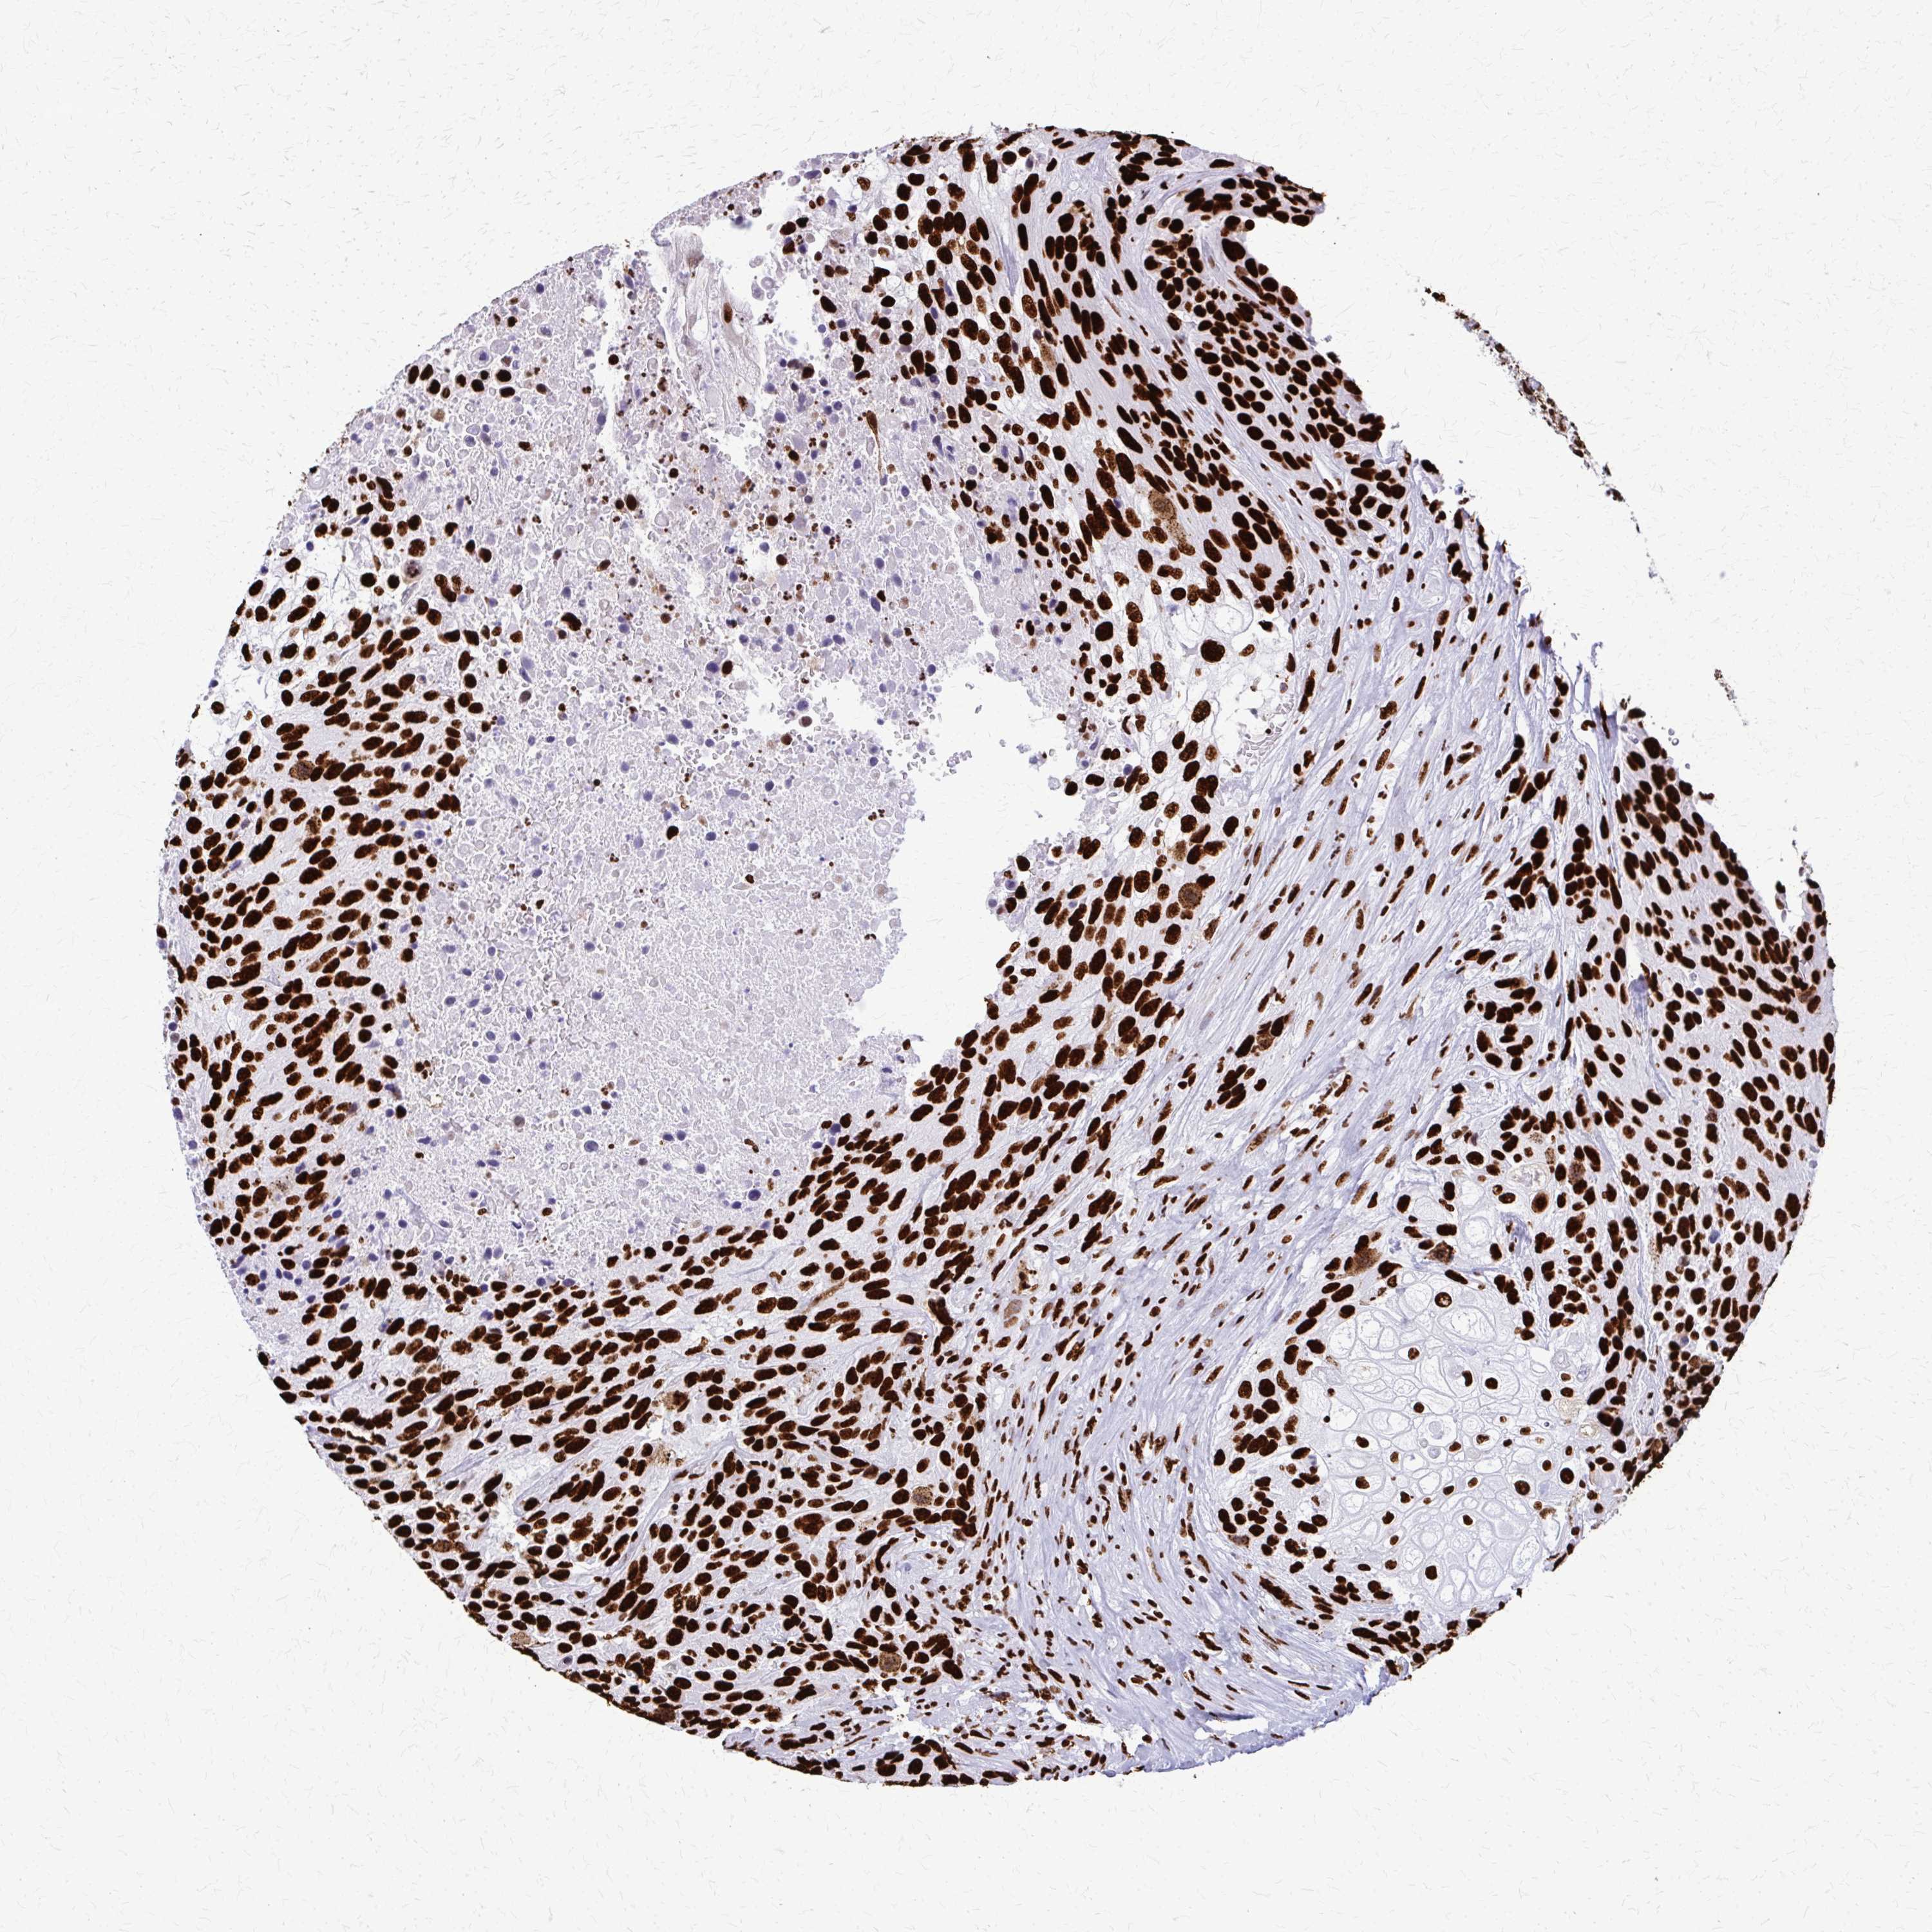

UROTHELIAL CANCER - Protein expressioni

A mouse-over function shows sample information and annotation data. Click on an image to view it in a full screen mode. Samples can be filtered based on level of antibody staining by selecting one or several of the following categories: high, medium, low and not detected. The assay and annotation is described here.

Note that samples used for immunohistochemistry by the Human Protein Atlas do not correspond to samples in the TCGA dataset.

Antibody stainingi

Antibody staining in the annotated cell types in the current human tissue is reported as not detected, low, medium, or high, based on conventional immunohistochemistry profiling in selected tissues. This score is based on the combination of the staining intensity and fraction of stained cells.

Each image is clickable and will lead to virtual microscopy that enables deeper exploration of all samples and also displays staining intensity scores, fraction scores and subcellular localization as well as patient and tissue information for each sample.

Antibody HPA047513

Antibody HPA054689

Antibody CAB009886

Staining

High

Medium

Low

Not detected

Intensity

Strong

Moderate

Weak

Negative

Quantity

>75%

75%-25%

<25%

None

Location

Nuclear

Cytoplasmic/membranous

Cytoplasmic/membranous,nuclear

Urothelial carcinoma, High grade

Urothelial carcinoma, Low grade